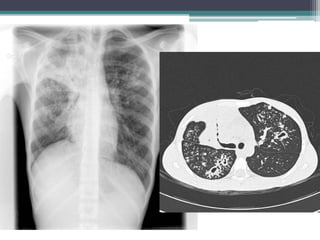

Radiografía tórax

Contactos íntimos: SIEMPRE

Independiente resultado Mantoux

Resto de casos: Mantoux +

Lactante 23 meses Niño de 5 años

Afectación parenquimatosa hiliar

izquierda.

Consolidación lobar superior incluida

língula

Niña 6 años

Consolidación lobar superior izquierda